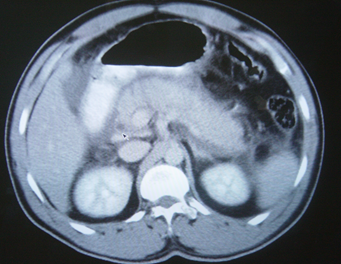

- Kontrastlı KT və ya MRT standart müayinədir, şişi və yayılma dərəcəsini müəyyənləşdirilməsində önəmlidir.

- Görüntüləmdə: erkən arterial fazada contrast tutan və venoz fazada yuyulan, MRT-də hipointens, ətraf toxumalara invaziv, böyüməyə meylli, baş nahiyyəsində yerləşərək xoledoxu və pankreatik axacağı genişləndirən (“iki axacaq simptomu”) törəmə